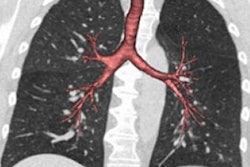

A 65-year-old man with severe lung emphysema (light blue on images below) seen on axial CT image (image 1 above), CT image including AI-based calculation (image 2), and 3D model (image 3). Extent of low-attenuation volume is seen inside green outline in both lungs in image 2. Purple outline in anterior right part of image 2 marks boundary between upper and middle lobes. Gray outline in image 2 correctly segments lower part of upper lobe and ensures that all lung tissue was considered. Also in image 2, orange outline denotes margin of tracheobronchial tree, and blue outline denotes margin of left lower lobe. All images courtesy of the AJR.Those results indicate that AI-based emphysema quantification meaningfully reflects clinical pulmonary physiology, according to the researchers.